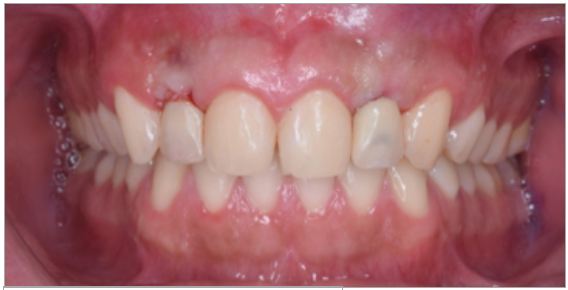

Paciente de sexo masculino de 24 años de edad, de raza mestiza, sin antecedentes sistémicos y oclusalmente estable, que fue transferido al servicio de Rehabilitación Oral del Posgrado y Especialización de la Universidad Peruana Cayetano Heredia, Lima, Perú. Recibió previamente tratamiento ortodóncico en el servicio de Ortodoncia y Ortopedia Maxilar por 6 años. Al examen intraoral presentó agenesia de las piezas 12 y 22 con evidencia de defectos óseos, presenta fenotipo periodontal grueso (figura 1). Al examen radiográfico se observa disminución generalizada de las raíces (Rizomicri), presenta ensanchamiento del ligamento periodontal generalizado (figura 2). Para el plan de trabajo para el diagnóstico se obtuvieron modelos de estudio primario, realizando el encerado para la planificación del tratamiento del sector anterosuperior. Al análisis tomográfico se evidenció poca disponibilidad ósea, motivo por el cual se planificó dos injertos en bloque de mentón con hueso particulado y plasma rico en plaquetas previo a la colocación de implantes dentales (figura 3 y figura 4). Pasado el tiempo de osteointegración (6 meses) se colocaron dos implantes Strong WS Cono Morse (SIN®, Sao Paulo, Brasil) de 3.5 mm x 11 mm. En la segunda fase, se confeccionaron provisionales de acrilico termocurado Vitalloy® (Vitacryl; A. Tarrillo Barba S.A., Lima, Perú) para el manejo de los tejidos blandos a nivel de las piezas 12 y 22, los cuales estuvieron fijados a un cilindro provisional de titanio (SIN®, Sao Paulo, Brasil) atornillado al implante, verificando la adaptación de este al implante mediante una radiografía periapical (figura 5). El cilindro fue recortado dando una altura de 6 mm, los provisionales fueron agujerados en el medio (figura 6), de tal forma que el cilindro calce en el medio del espacio edéntulo, se cubrió la entrada del cilindro con teflón (Golfo USA®) y se capturó el cilindro con acrílico de autocurado Duralay color 62 (Reliance Dental Manufacturing LLC, Illinois USA) (figura 7). Después del acrilizado se retiró el provisional, en la parte cervical se realizó un incrementó con resina fluida (Filtek™ Z350XT Flow - 3M ESPE Dental Products. St. Paul, Minnesota, USA) formando el contorno crítico a 2mm por debajo del zenit de los incisivos centrales de tal manera que entre los zenits de los incisivos centrales, laterales y caninos formen una zona triangular. El contorno subcrítico se realizó de forma convexa (figura 7 y figura 8). Se finalizó con el acabado y pulido del provisional con gomas de grano grueso (gris) y grano fino (verde) (Politip, Ivoclar-Vivadent; Schaan, Liechtenstein). Se manejó la conformación de los tejidos blandos en 2 citas mediante la adición por capas de resina compuesta (Filtek™ Z350 - 3M ESPE Dental Products. St. Paul, Minnesota, USA) a nivel del contorno crítico y subcrítico a las 2 semanas y 4 semanas de la instalación del provisional (figura 9 y figura 10). Se logró conformar las papilas interdentales, el contorno crítico y subcrítico observando que los tejidos se encontraran estables, sin inflamación, con el color de la encía igual a la encía adyacente; todo esto nos indicó que se podía realizar la impresión definitiva. La instalación final se realizó con coronas metal cerámicas cementadas (figura 11 y figura 12).